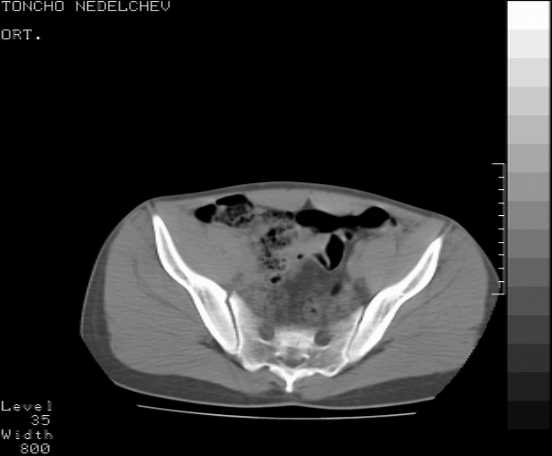

The details of the fracture are not so clear from the images sent...would you be able to send along an AP and Judet images as well as some additional axial images above and below the joint?

I’m not so sure that your patient has a Tr+PW pattern based on the images sent...maybe the fracture’s exact name won’t matter in the long run, but it’d be great to see enough images to make an accurate comment.

Without complete CT images and/or oblique radiographs, it's difficult to answer your question definitively, but it appears that there may not be a posterior wall fracture that requires a posterior approach. A successful reduction through an ilio-inguinal approach will have a faster recovery, and not risk SGN injury or heterotopic ossification.

Here are some more axial images. What is your opinion as for the timing of the operative treatment?